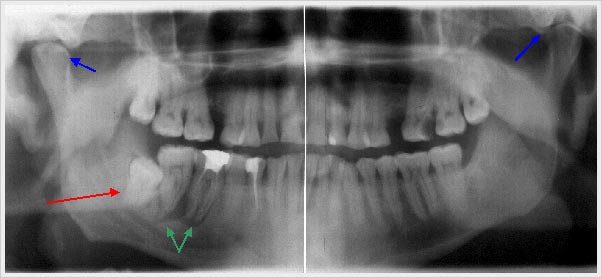

A mandatory part is also a x-ray of the whole jaw region (panoramic radiograph) in order to exclude dental and/or a dental operative cause of disease (e. g. displaced teeth, chronic infections of teeth roots, hidden decay or bone deterioration caused by parodontitis).

Panoramic radiograph

with displaced tooth (tooth 48 = right wisdom tooth) -red arrow-of chronic apicale parodontitis of teeth 46 and 47 -green arrows-

and also an indication of differences in jaw joints -blue arrows-